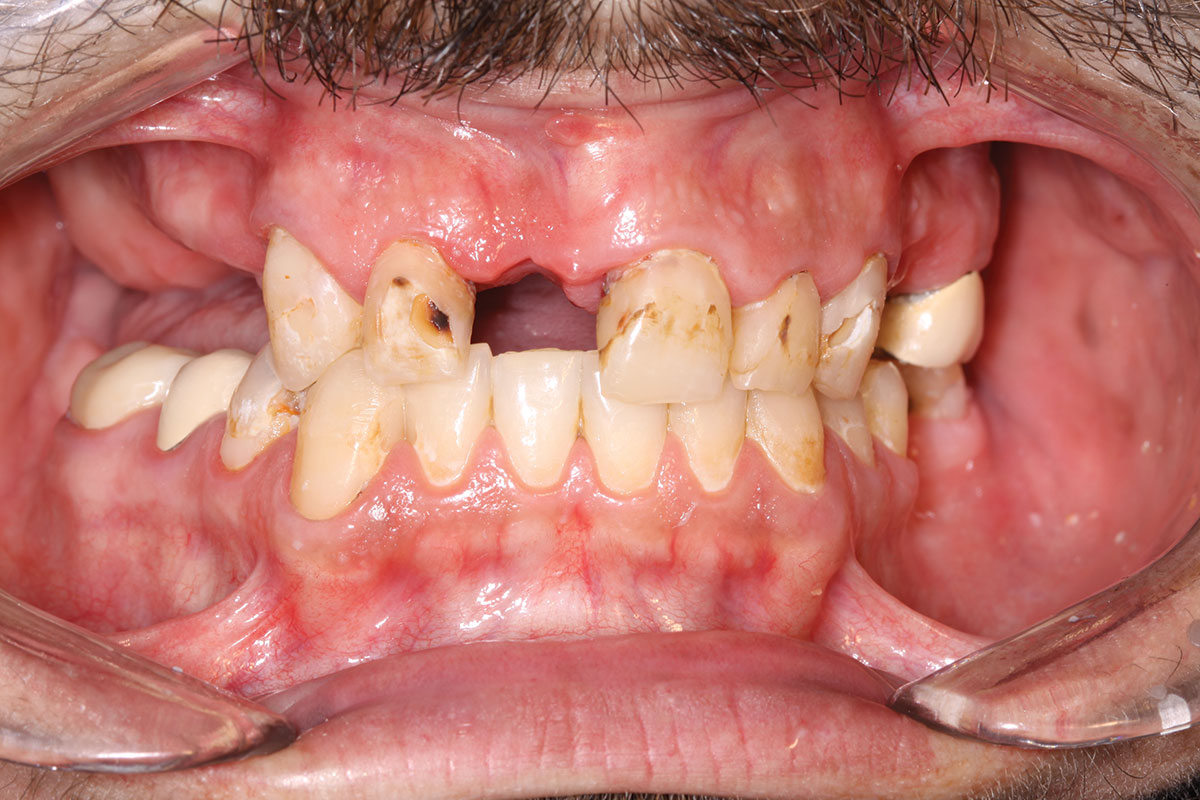

Fig 9. Case 2: Initial presentation for maxillary immediate implant, immediate load provisional restoration. Full-face photograph.

Figure 9

Fig 10. Initial clinical situation, intraoral view.

Figure 10

A 60-year-old female patient presented with many periodontally and restoratively hopeless teeth that severely compromised esthetics and function and were inadequate to retain a maxillary restoration. She declined to advance into a full maxillary denture or partial denture. Existing maxillary teeth included Nos. 2 and 4 through 14 (Figure 9 and Figure 10). The opposing dentition was stable. The patient was in good health with no allergies to medication.